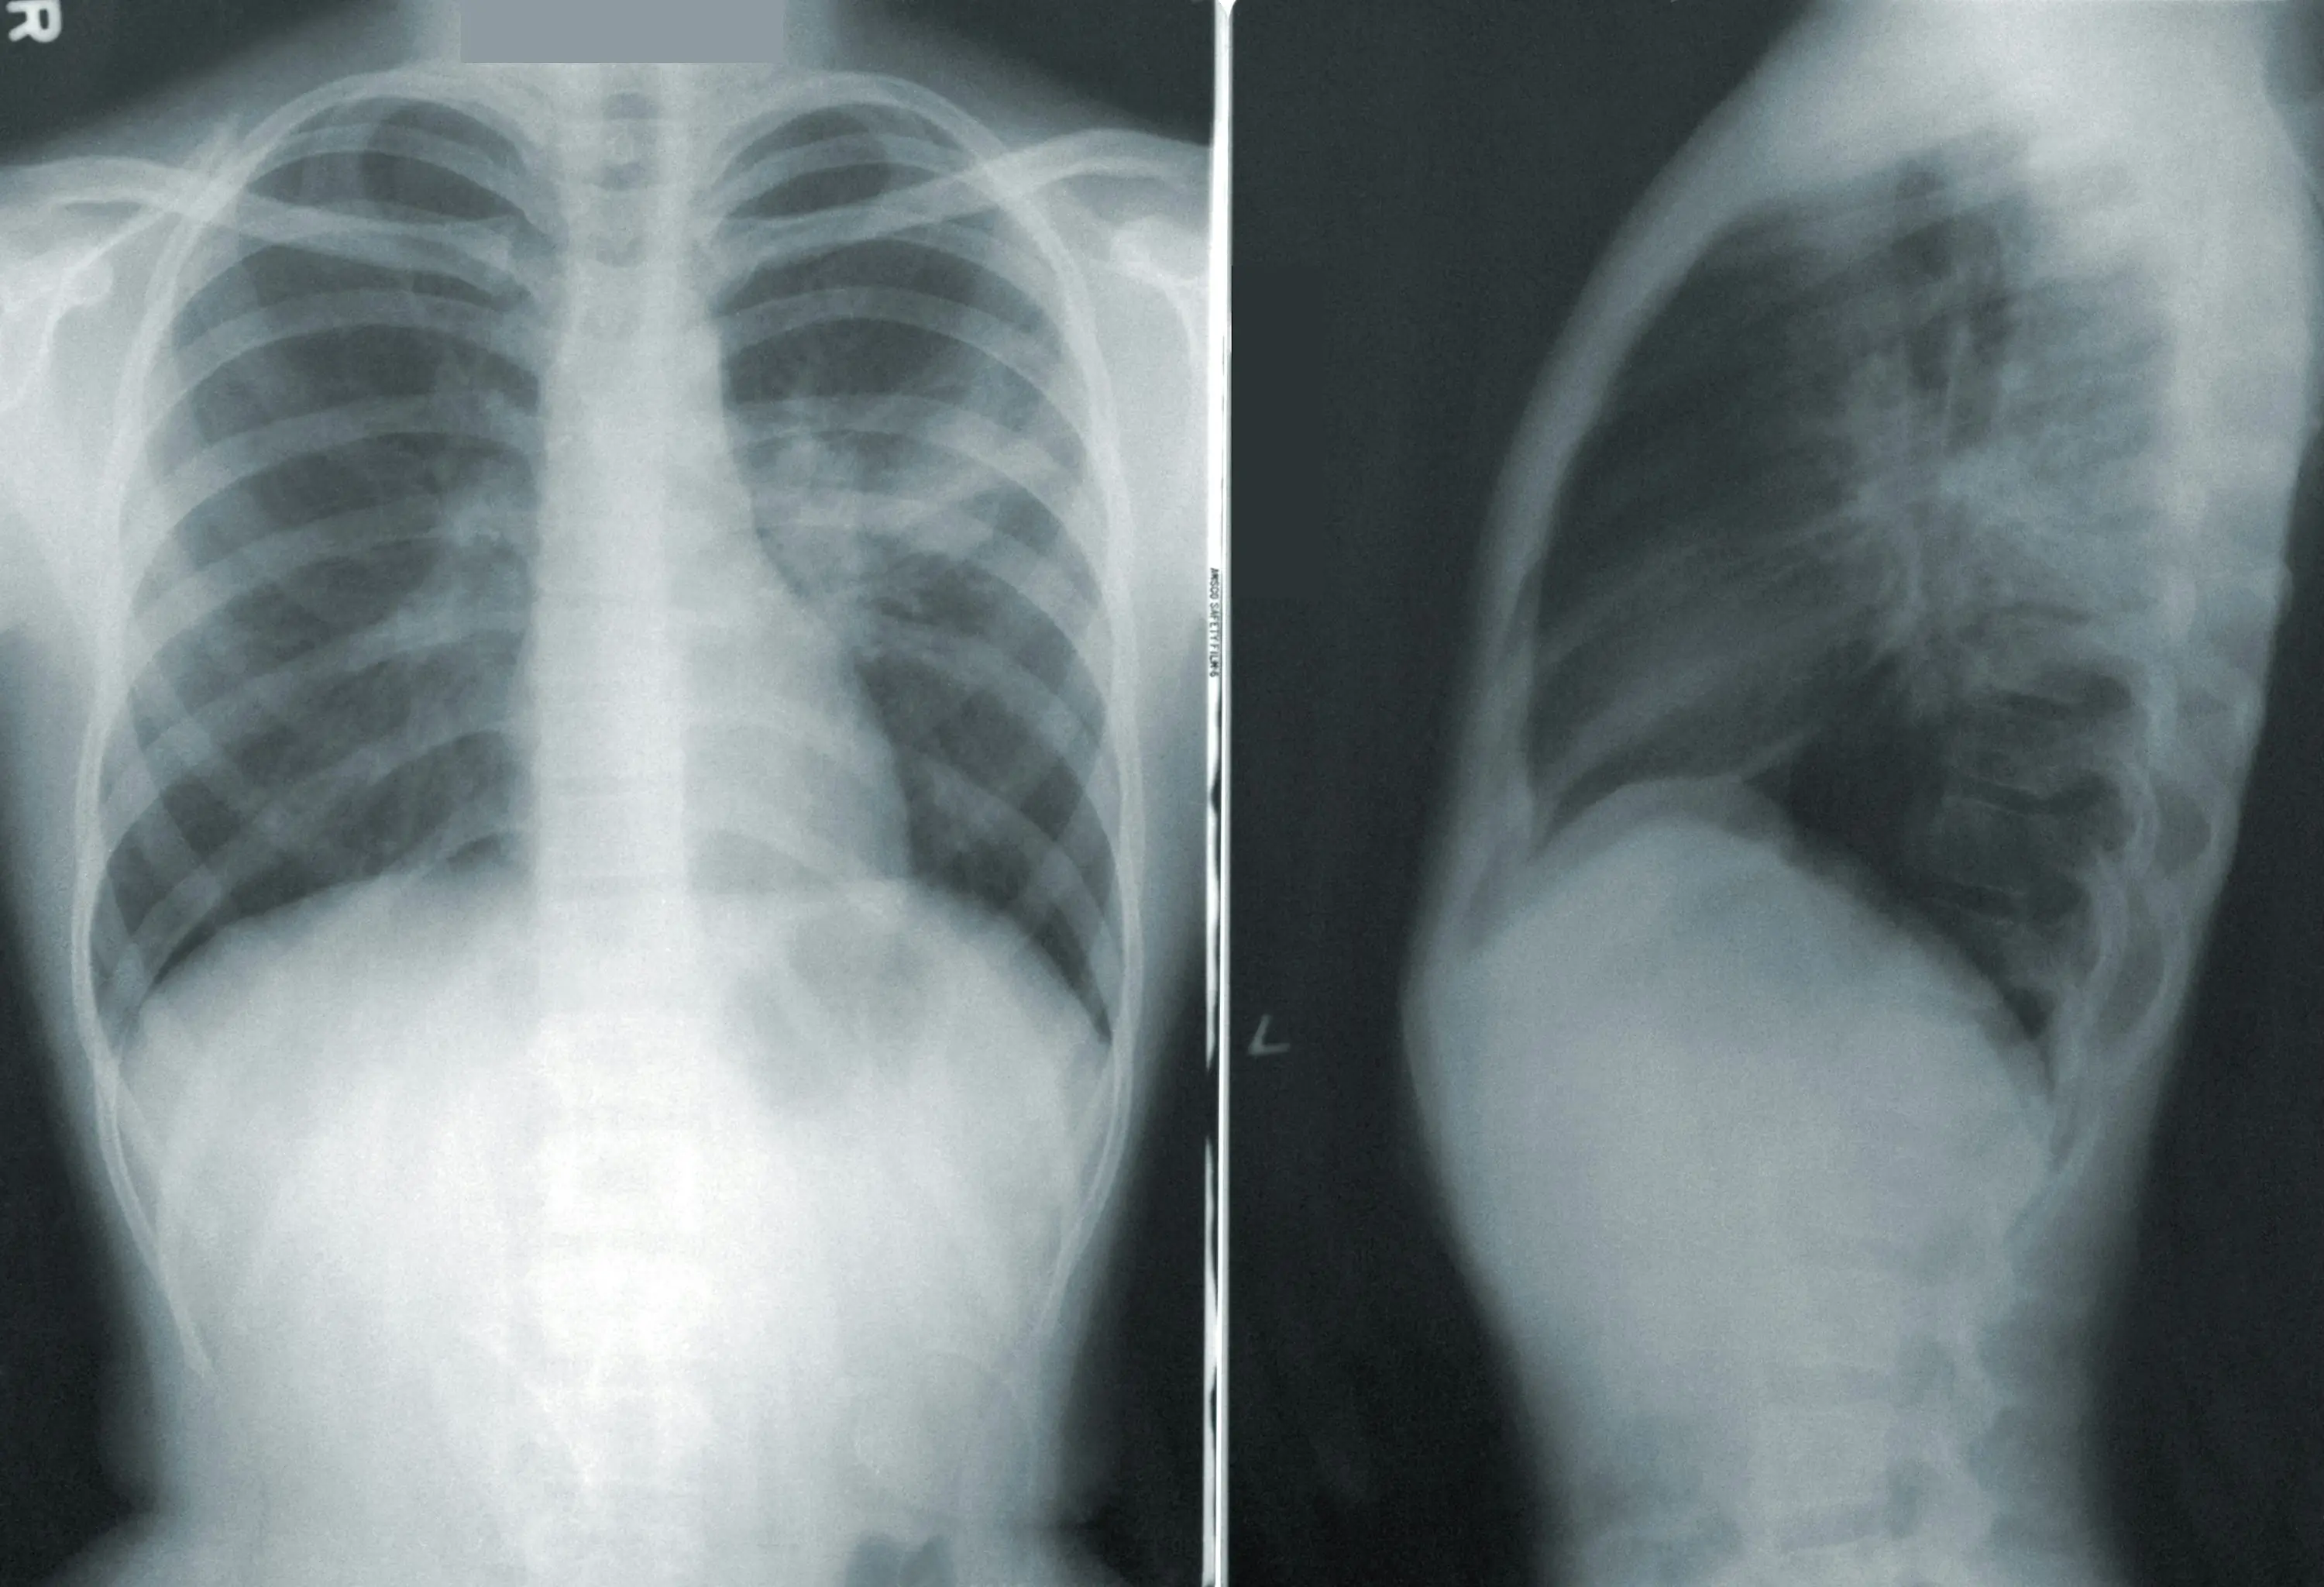

최근 의료계에서 주목받고 있는 질환 중 하나가 마이코플라즈마 폐렴입니다. 이는 전염성이 강한 폐렴의 일종으로, 특히 어린이와 노약자, 면역력이 약한 사람들 사이에서 확산되며 관심이 집중되고 있습니다.

마이코플라즈마 폐렴은 바이러스와는 달리 세균성 질환으로 항생제 치료가 가능합니다. 그러나 증상이 서서히 진행되고, 감염의 확산 속도가 빠르기 때문에 진단 및 치료 과정에서 의료 관련 기업들이 적극적으로 나설 필요가 있습니다.